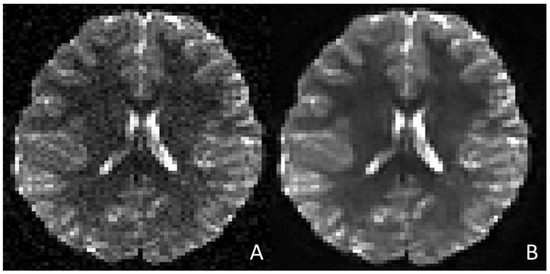

- Kim, S.-H.; Choi, Y.H.; Lee, J.S.; Lee, S.B.; Cho, Y.J.; Lee, S.H.; Shin, S.-M.; Cheon, J.-E. Deep Learning Reconstruction in Pediatric Brain MRI: Comparison of Image Quality with Conventional T2-Weighted MRI. Neuroradiology 2023, 65, 207–214. [Google Scholar] [CrossRef] [PubMed]